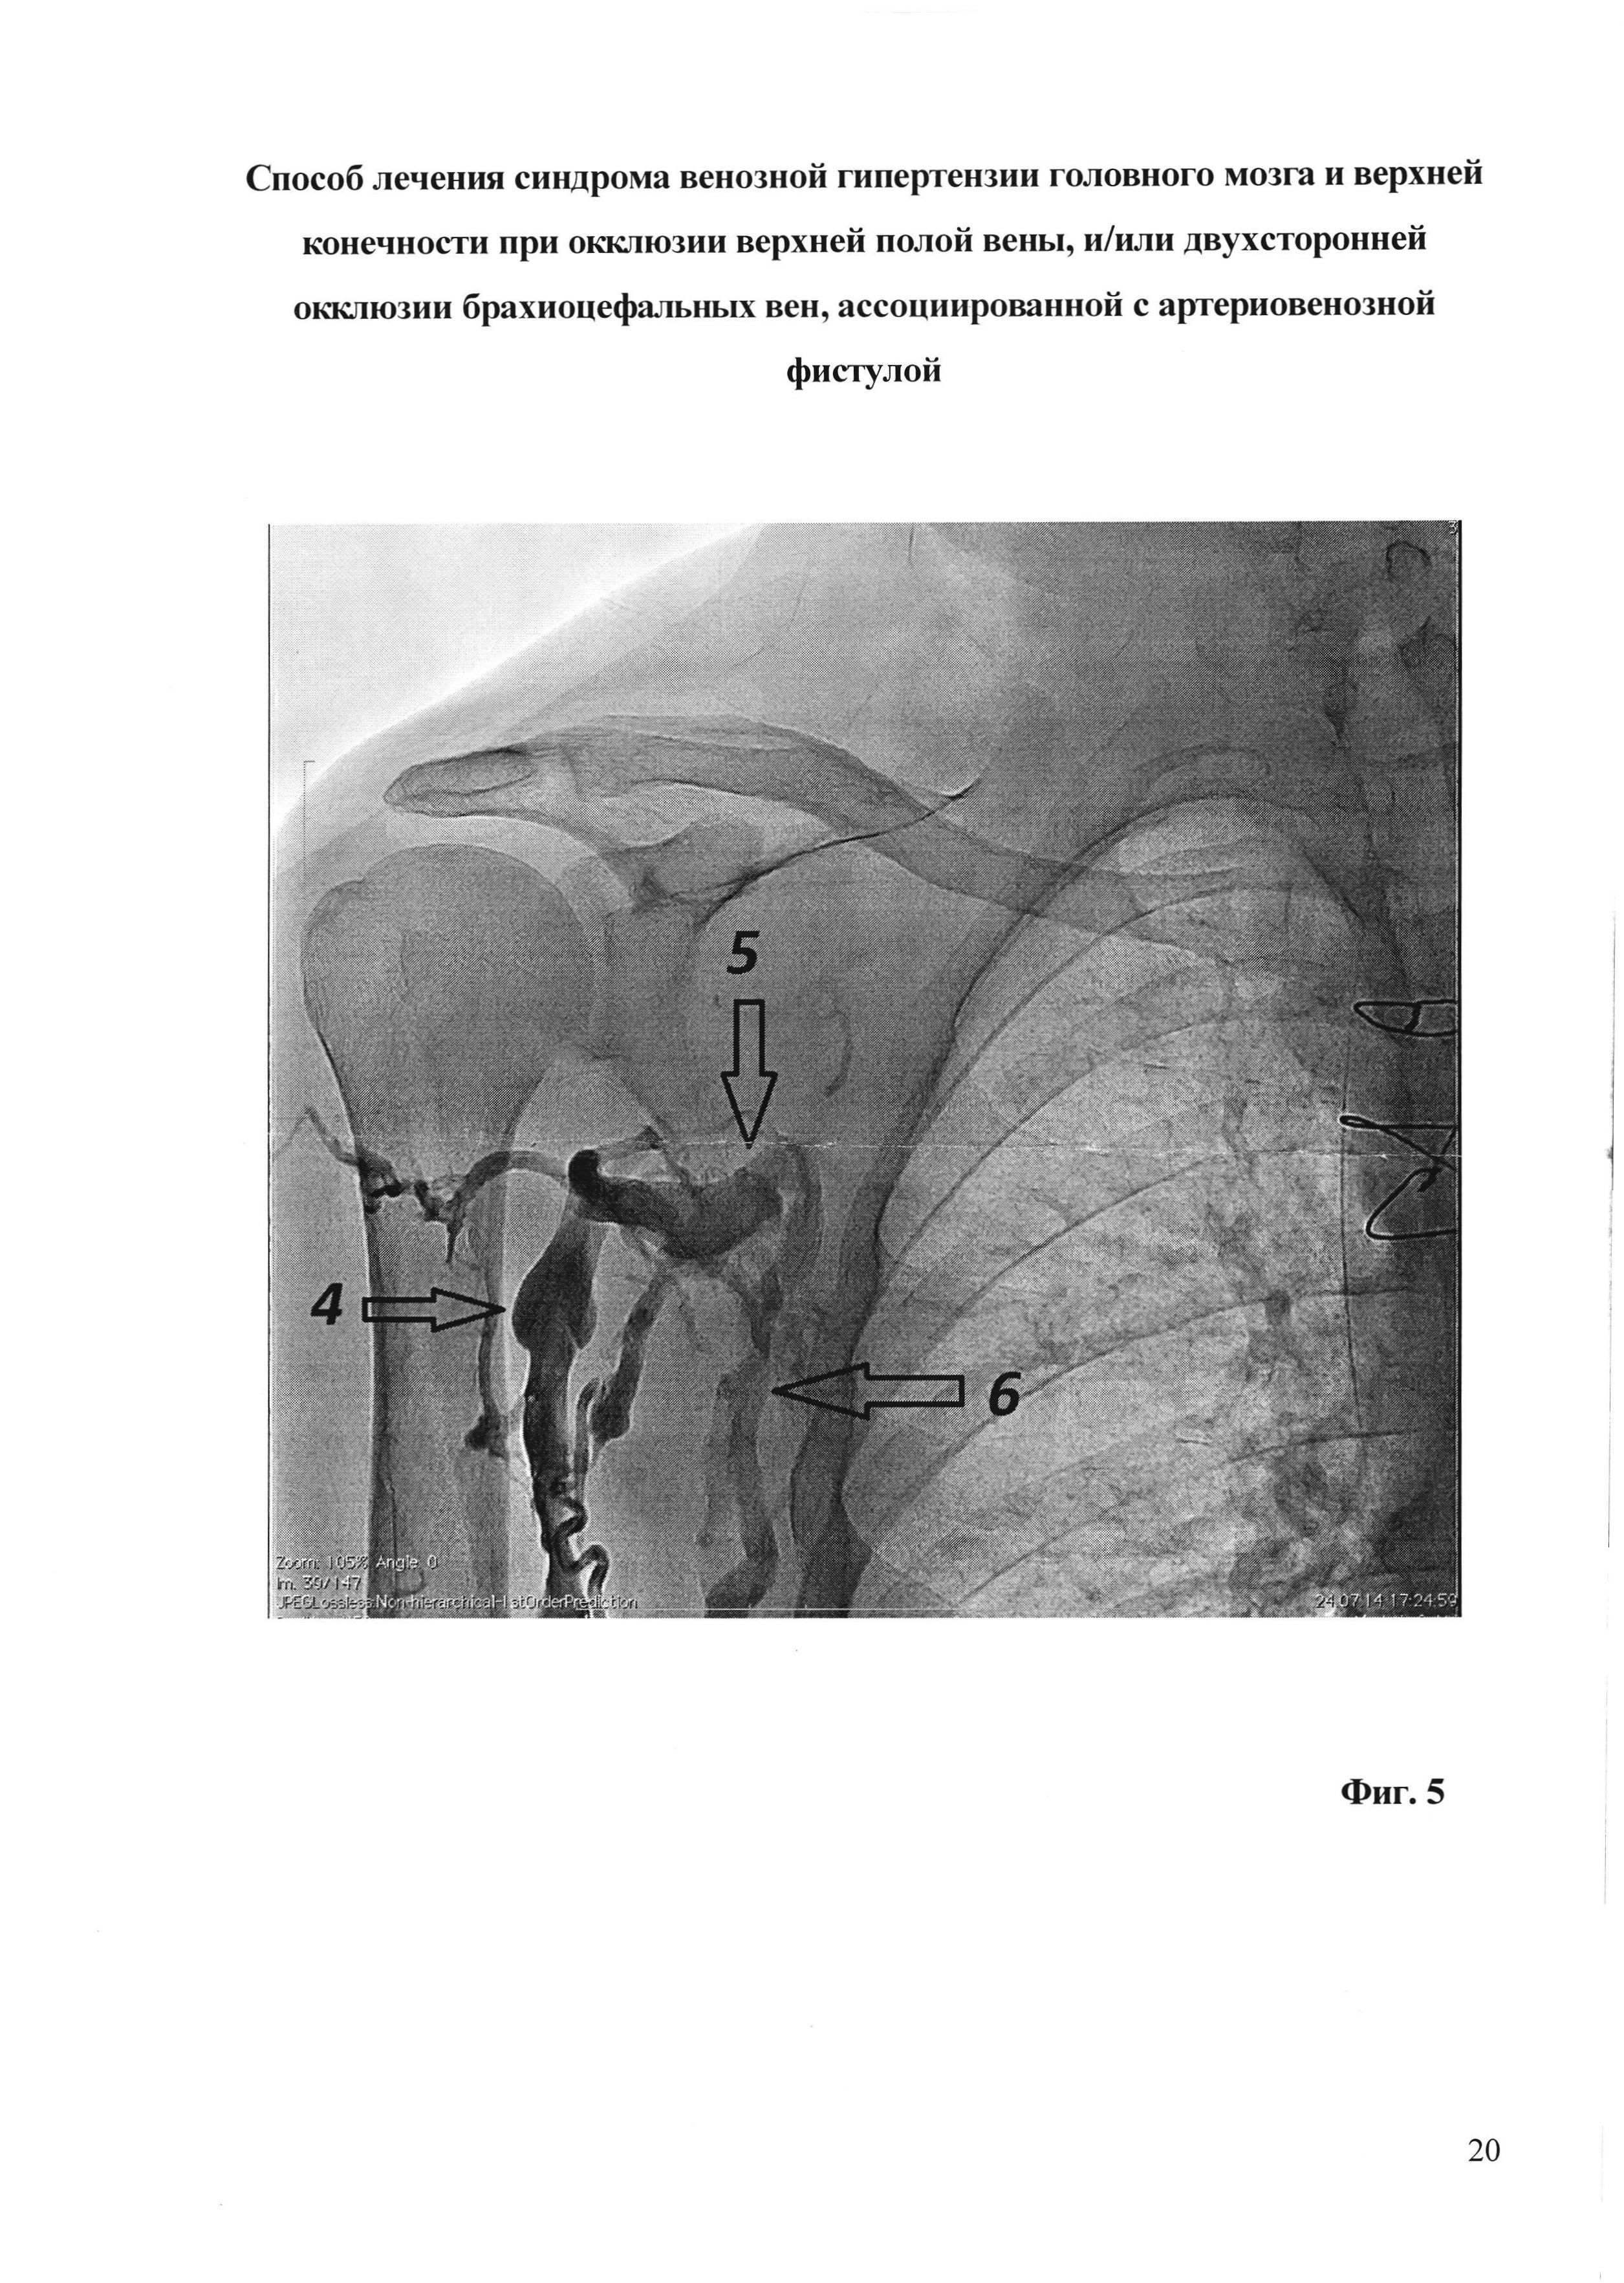

[29]

На фиг. 5 - флебограмма брахиоцефальных вен и вен правой верхней конечности пациента М. до операции; 4 - правая v. cephalica, 5 - правая подмышечная линия вена, 6 - правая v. basilica. Не контрастируются правая подключичная вена, правая брахиоцефальная вена и верхняя полая вена.